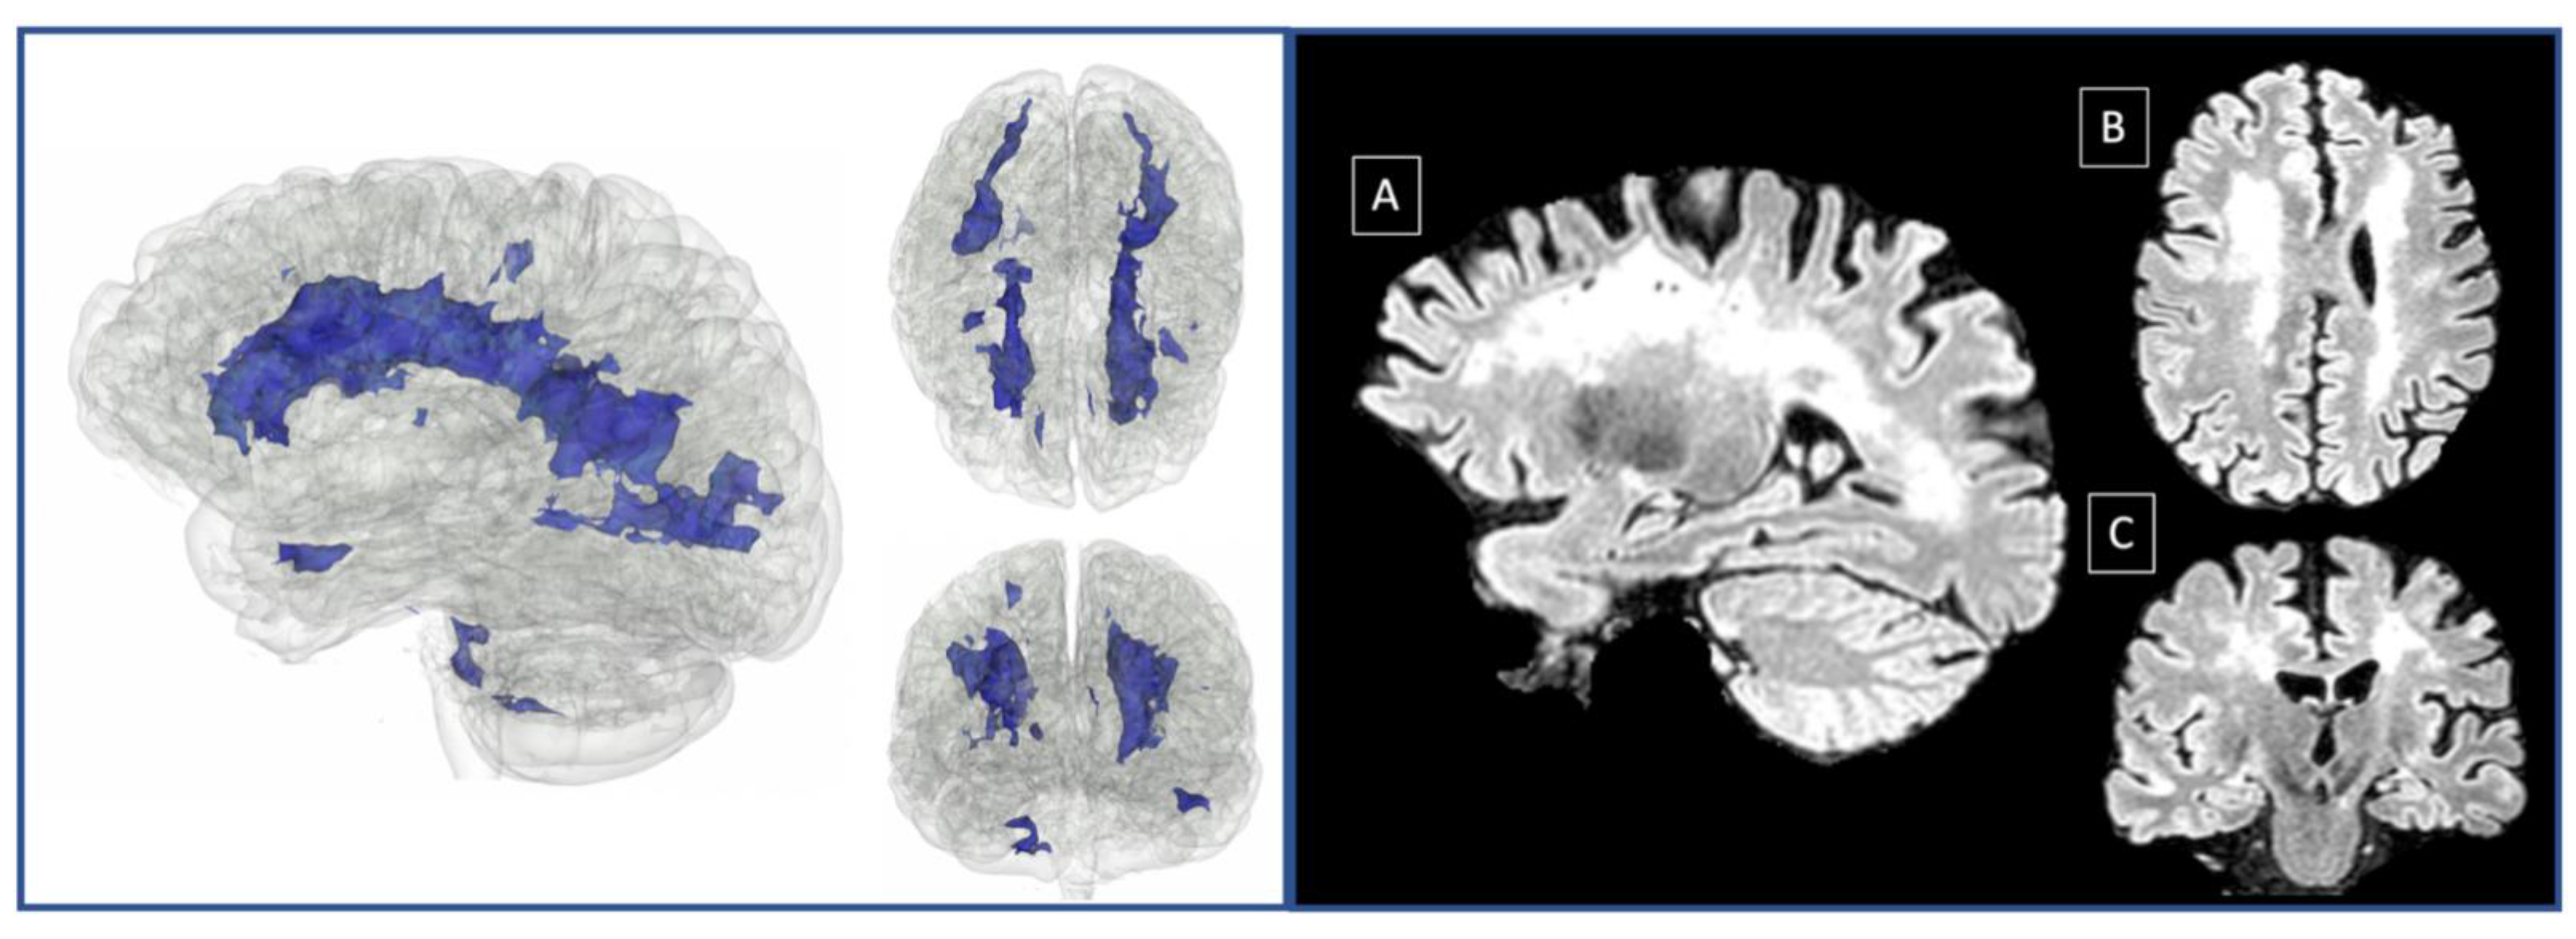

Only P3 exhibited an impaired performance in episodic memory, which could be at least partly attributed to her generalized cognitive decline. As for the language domain, there were patients who showed deficits in several linguistic aspects; however, we could only speculate about their origin. For example, for P1, P3, P4, and P5, impaired scores could be attributed to the left-lateralized ischemic lesions, but this was not the case for P6. An alternative explanation for language deficits could be based on the diffuse white matter lesions found in MMD patients (see Figure 3). Finally, verbal working memory was found to be systematically affected in our group.

Figure 3. White matter lesions 3D model in native space (left). Saggital (A), axial (B) and coronal (C) view of 3D Flair in native space (right). The three-dimensional (3D) brain model was built from a patient’s (P6) 3D Flair (Repetition time (TR): 4800 ms, Echo Time (|TE): 284 ms, slice thickness 1.48 mm, flip angle: 90, sagittal orientation) in native space, using the Model Maker Module, in 3D slicer version 4.11.2 [56]. White matter lesions were automatically detected with 3D Flair as input, using Lesion Spotlight extension [57,58] run on 3D slicer.

Overall, our study confirms previous reports highlighting executive impairment in MMD, and adds additional information about the cognitive profiles of such patients by revealing deficits in working memory and social cognition. Here, it should be noted that there are sparse studies assessing social cognition of MMD patients [17,18]. To the best of our knowledge, this is the first study reporting impaired performance in social cognition, and particularly theory of mind, in a case series of Caucasians with MMD. A lingering question concerns the co-occurrence of deficits in executive functions, working memory, and social cognition in MMD. A possible explanation of the observed co-morbidity of impaired social cognition and dysexecutive phenomenology could be based on the fact that executive functions are presumably associated with theory of mind in terms of anatomy and function [34]. A more through hypothesis could be formulated on the basis of the anatomical substrate of working memory, social cognition, and executive functions, in conjunction with the lesional pattern of MMD. Brain imaging studies point to a widely distributed network, comprising of posterior, anterior, as well as underlying white matter, which supports executive functions ([40,41]; for a review, see [42]). On the other hand, meta-analyses highlight the importance of a fronto-parietal network as the neurobiological substrate of WM [43,44]. This notion is further supported by studies investigating individual components of working memory, and demonstrates that these are associated with the posterior parietal cortex, as well as the dorsolateral and ventrolateral prefrontal cortex [45,46,47]. With regard to the neural correlates of social cognition, the reported evidence may be yet inconclusive, but the emerging trend is in favor of a distributed network supporting this particular psychological construct, since brain imaging studies reveal that performance on relevant tasks (e.g.,theory of mind tests) elicit hemodynamic responses in the medial prefrontal cortex, the orbitofrontal cortex, the temporal pole, the temporoparietal junction, and the superior temporal sulcus [48,49,50,51,52,53]. In sum, all of the aforementioned cognitive domains cannot be linked to a single brain area but are rather associated with a broader network of cortical and subcortical brain regions. MMD, on the other hand, is a neurological disorder that results in diffuse lesions mostly affecting white matter tracts (see Figure 3). In this sense, following Campbell’s hodological approach, according to which corticocortical connectivity is crucial for higher cognitive functions [54], we could adopt the hodotopic framework proposed by Catani and Ffytche [55]. Within this framework, the neurocognitive pattern of MMD could be interpreted as a result of white matter lesions (in synergy with cortical lesions due to circumstantial strokes), that consequently affect the above-described networks supporting the three cognitive domains. This view is in line with evidence showing that cognitive dysfunction can be seen also in MMD patients without stroke, i.e., without cortical damage [12,38].